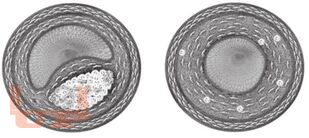

Кардиология детского возраста является быстро прогрессирующей областью педиатрии. В монографии в виде лекционного материала обобщены актуальные разделы кардиологии детского возраста. Автор сконцентрировал внимание на наименее изученных разделах кардиологии детского возраста, их выбор был определен как многолетним опытом работы автора по этим проблемам, так и недостаточной освещенностью этих разделов детской кардиологии в литературе. Автор подробно осветил проблемы диагностики и лечения заболеваний миокарда, и перикарда, основы патогенеза и тактики лечения сердечной недостаточности, проблемы артериальной гипертонии и артериальной гипотонии, а также профилактики факторов риска возникновения сердечнососудистой патологии, рассмотрены механизмы возникновения и тактика ведения детей с синкопальными состояниями. Лекции по детской кардиологии предназначены для практической работы педиатров, детских кардиологов, подготовки студентов, ординаторов и аспирантов медицинских вузов и научноисследовательских институтов.